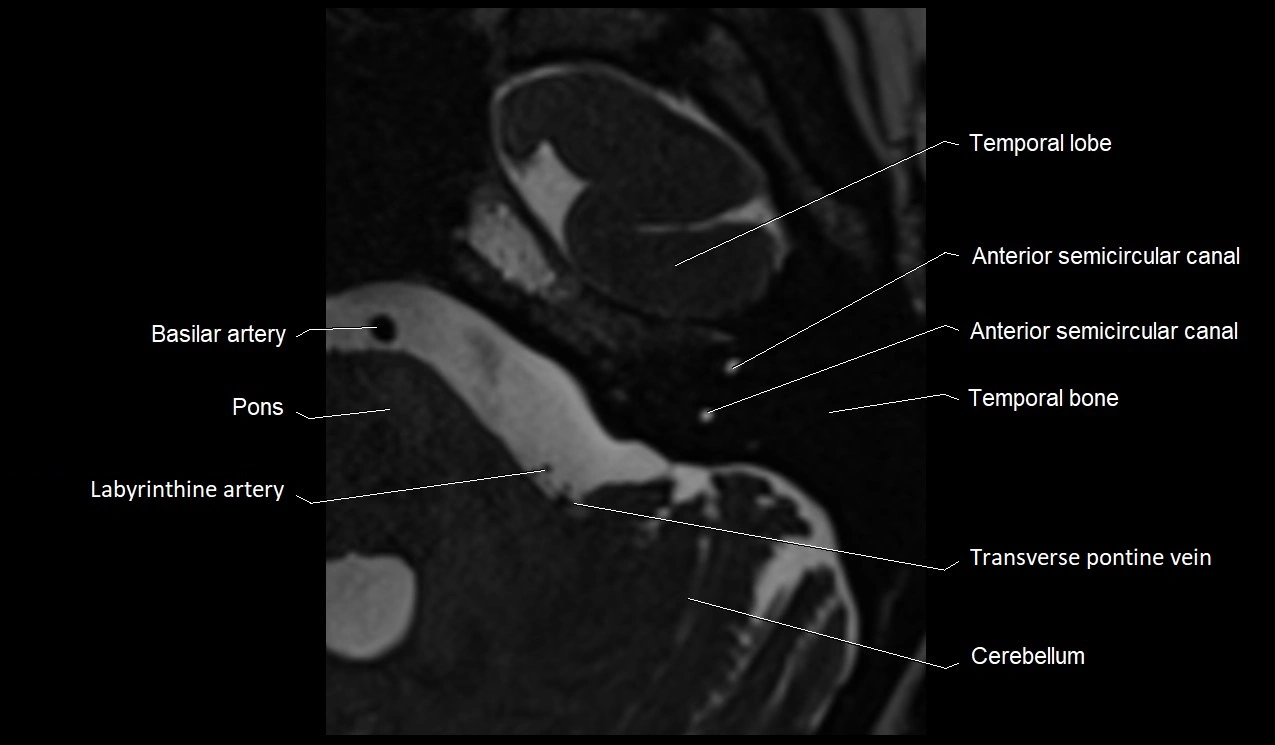

MRI Appearance

• The abducens nerve is a small, thin, linear structure

• Best visualized on high-resolution T2-weighted 3D MRI sequences (e.g., FIESTA or CISS)

• Seen as a hypointense (dark) line running from the brainstem at the pontomedullary junction, traversing the prepontine cistern, and entering Dorello’s canal under the petrosphenoidal ligament, then into the cavernous sinus, and finally the orbit

• May be challenging to visualize in standard MRI due to its small size

• Pathology may be inferred by absence, displacement, or enhancement of the nerve

MRI images

image